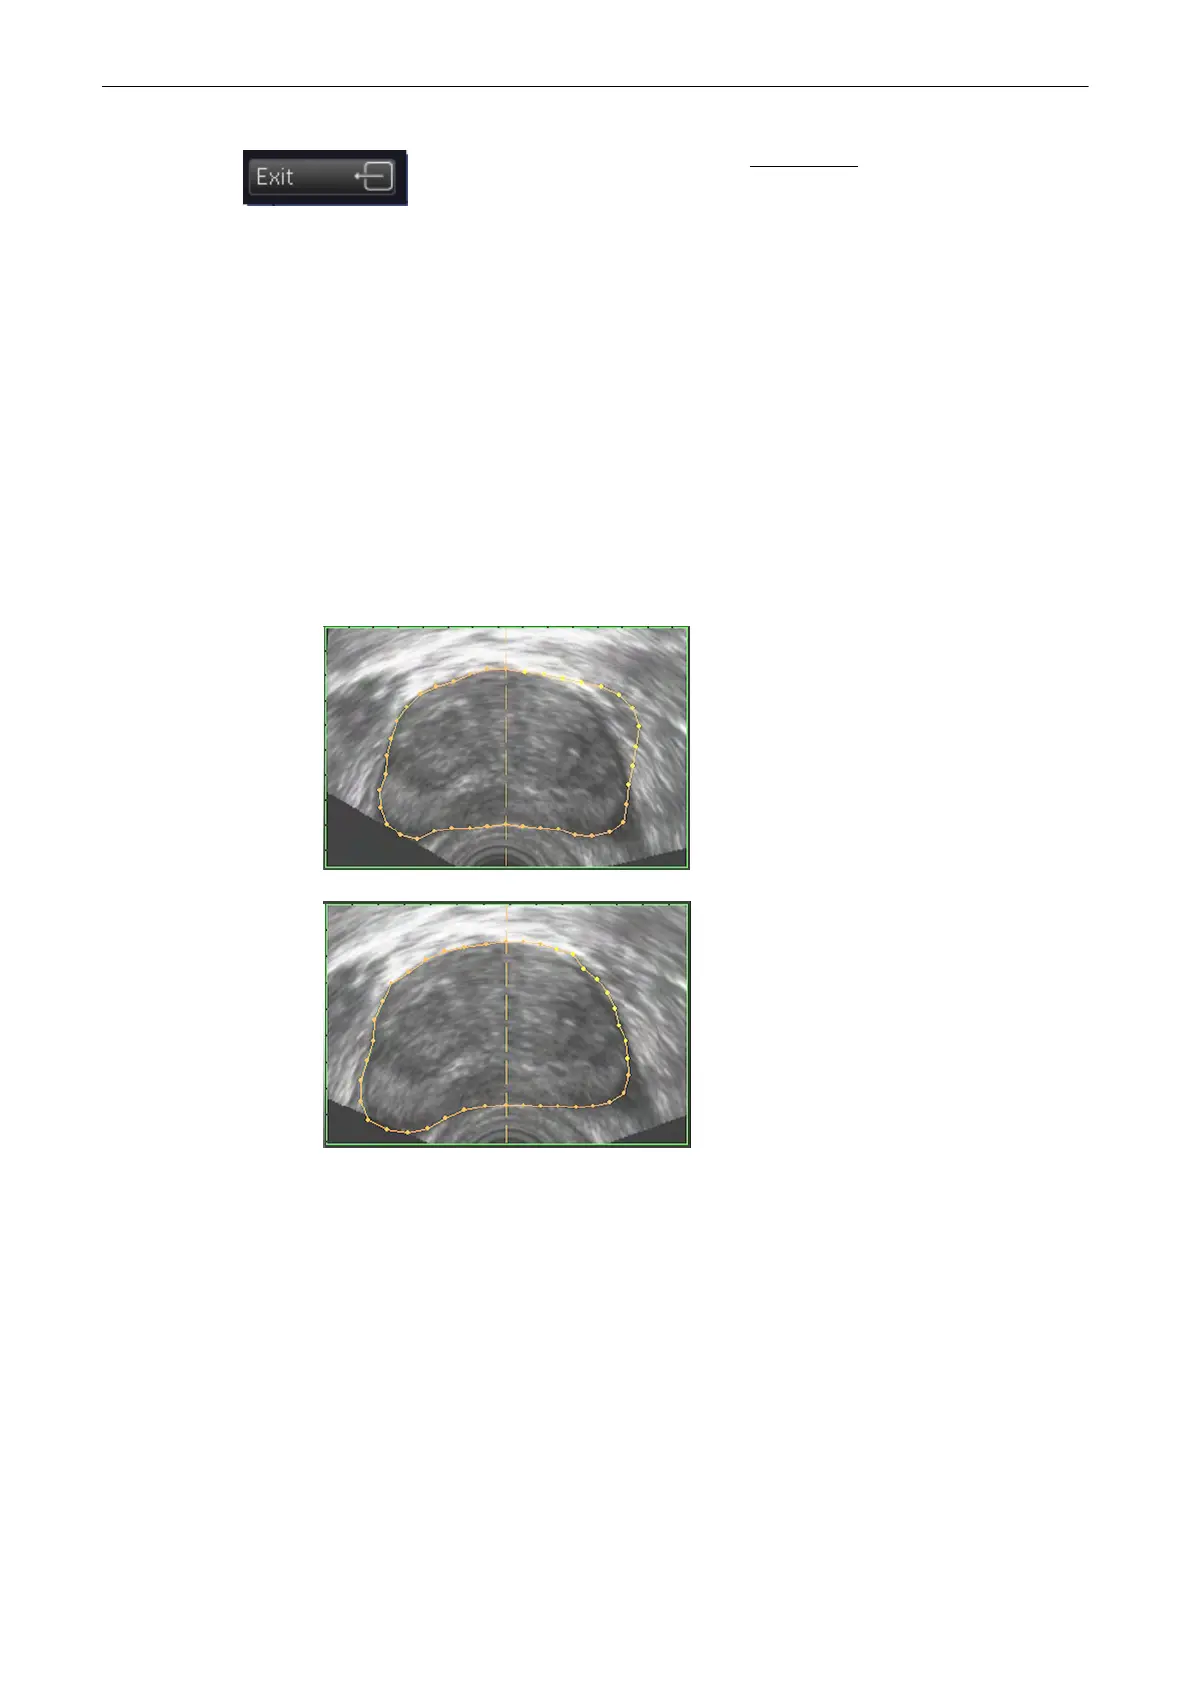

The monitor screen appears as follows:

The reference image shows the first generated contour, outlined with red and yellow

dots.

In the orthogonal slices the intersection curves between the shell geometry and the

different image planes are outlined as a yellow contour.

The shell geometry is visualized in the lower right quadrant.